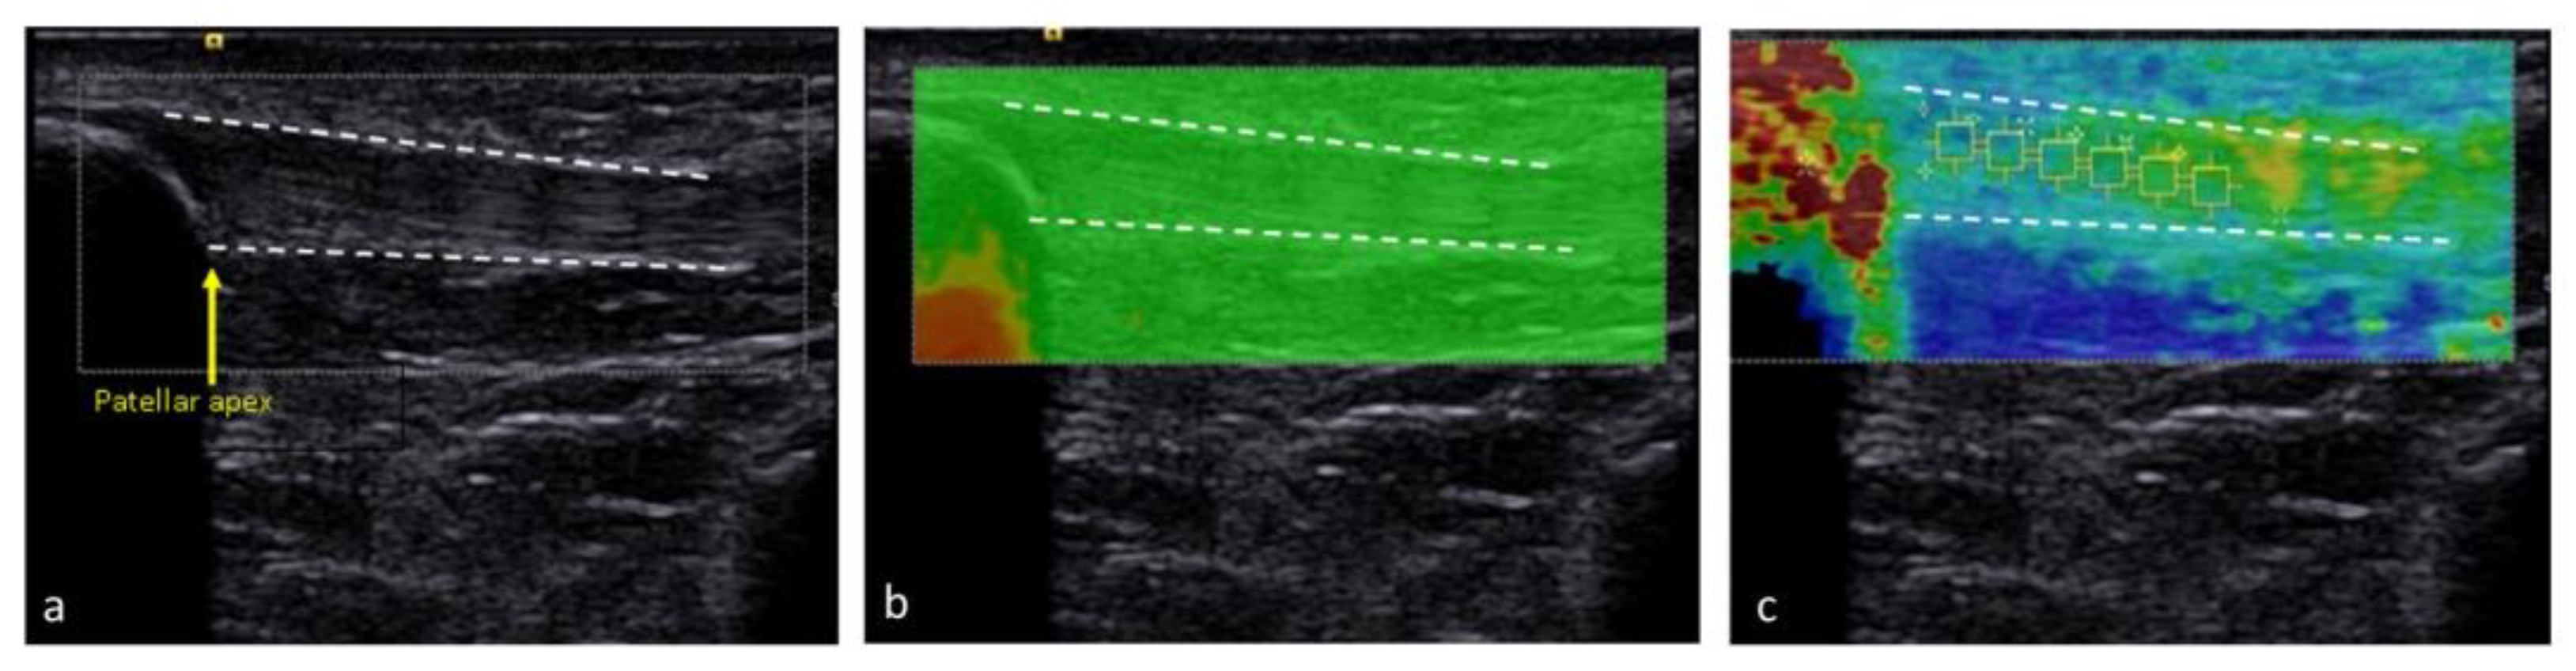

2.3. Ultrasound Examination Protocol